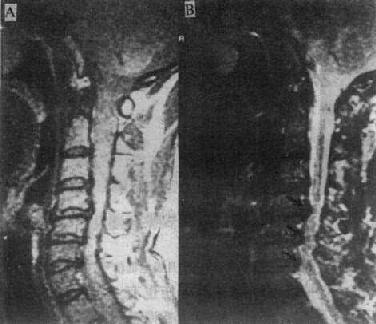

MRI可清楚地显示椎管狭窄,包括椎体与脊椎小关节的增生、韧带肥厚和椎间盘脱出等。如果椎间盘脱出发生在多个平面,且相对的黄韧带肥厚,则在与椎间隙水平相对应的硬膜囊前后缘受压,在矢状面T2WI上,硬膜囊呈串珠状表现(图2-2-4)。

质子密度像 T2WI

图2-2-4p; 颈椎关节病颈4~6段的蛛网膜下腔及脊髓于椎间盘水平均受压变细,呈典型的糖葫芦状

在脊柱外伤,MRI可用以观察椎体骨折,椎间盘脱出和韧带撕裂。同时还可观察脊髓挫裂伤和脊髓受压等,诊断价值高。在脊椎化脓性骨髓炎,MRI可观察炎症是否累及椎间盘,如受累,则椎间盘与椎体分界不清,在T1WI上均呈低信号,而在T2WI上则呈高信号。